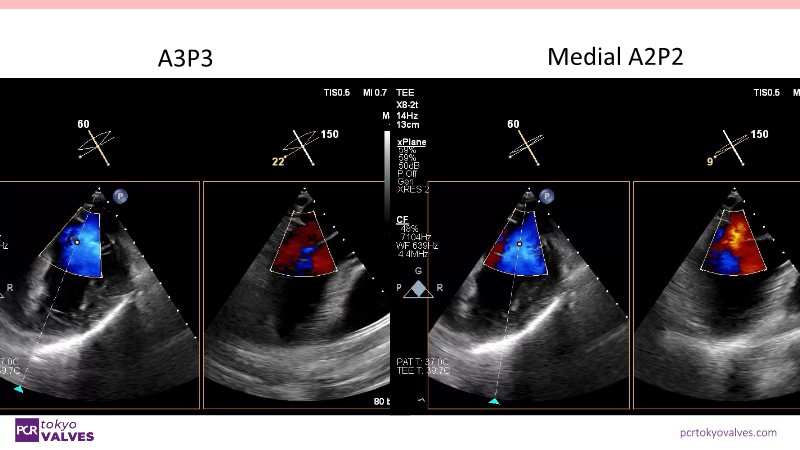

Explore the latest advancements in TEER therapy with this PCR Tokyo Valves 2025 session dedicated to MitraClip. Through expert-led case discussions, gain a deeper understanding of complex scenarios, including restricted posterior leaflet in functional mitral regurgitation, commissure lesion (A3P3), and MitraClip combined with Amulet.